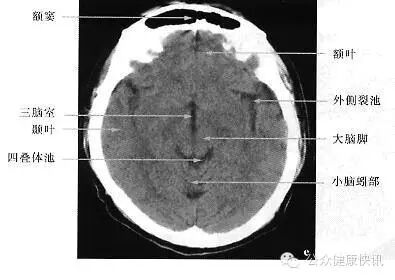

这是头颅CT正常情况。

CT

用X线给身体每个横截面“拍照”

特长:成像比X线更清晰;对高密度的骨性组织和出血、肿瘤的钙化病变的检出,具有独特优势。低剂量的螺旋CT是对肺癌筛查的有效手段。